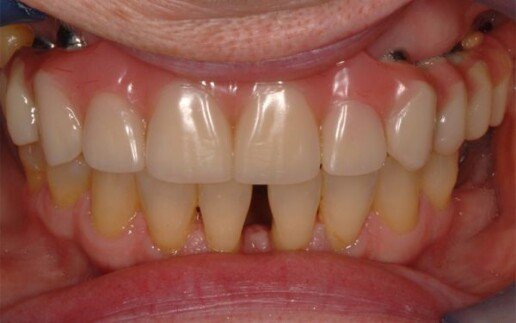

Riabilitazione totale superiore e inferiore su impianti. Gli esiti di una paradontite grave portano alla perdita totale dei denti. E’ necessario ricostruire sia i denti sia i tessuti molli e anche l’osso per il sostegno delle labbra.

Prima

Dopo